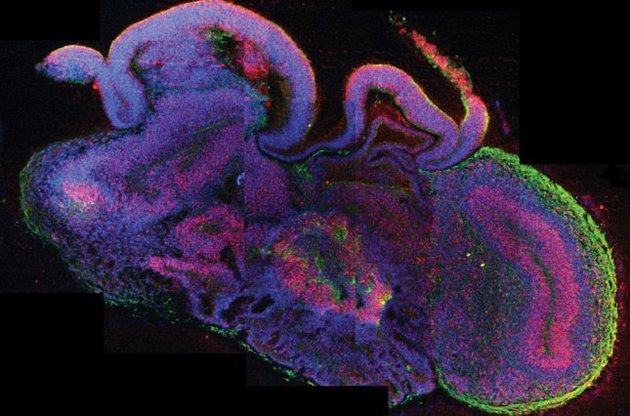

Ученые вырастили в пробирке миниатюрный мозг человека

Ученые Эдинбурга и Вены вырастили миниатюрный мозг человека в пробирке. Исследователи ожидают, что он послужит отличной моделью, имитирующей естественное строение мозга, для изучения ряда заболеваний и испытаний потенциальных лекарств.

Образцы размером всего в несколько миллиметров построены из слоев клеток головного мозга, которые максимально приближены к его строению в эмбриональной стадии (в возрасте около девяти недель), пишет The Guardian.

Ткани мозга сформировали четко разделенные между собой структуры, напоминающие кору, сетчатку и структуры, производящие спинномозговую жидкость.

В настоящее время структурные образования не могут достигать больших размеров, так как питательные вещества и кислород не смогут проникать в центральные отделы без кровоснабжения или другой системы обеспечения питания.

Ученые убеждены, что такие органы не смогут полноценно выполнять большинство функций мозга. Однако они позволят исследователям наблюдать, как органы развиваются в матке, и поможет диагностировать неврологические и психические проблемы, такие как шизофрения и аутизм, на ранних стадиях.